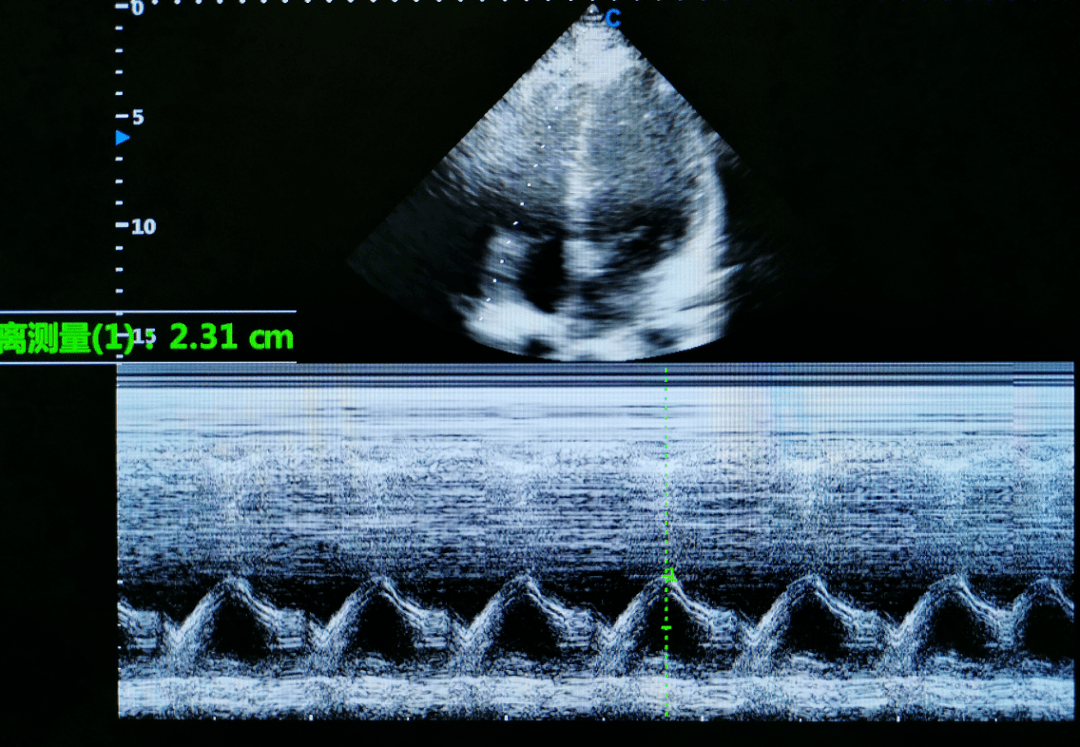

功能评估与左心室相同,采用脉冲多普勒法于三尖瓣上测量舒张期频谱(图

图片尺寸1080x747